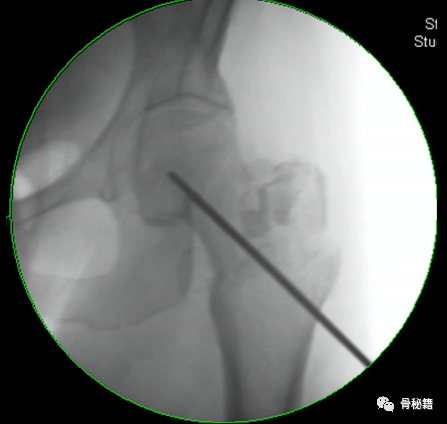

1、进钉点。髓内钉的位置在哪里最合适?

当然是髓腔的最中心,所以髓腔最中心的延长线就是最佳的进钉点。一般位于梨状窝。一个好的进针点可以保证力线,同时进钉后还有复位的作用,如果进钉点出现了偏移,可能整个手术都会有影响。好的开始象征着接下来手术的顺利,一定要取一个好的进针点。

他在正侧位的透视位置我们可以看到位于髓腔中心的延长线上

随着有外翻角的髓内钉的发明,我们现在目前用的可能多是大粗隆顶点进针的了